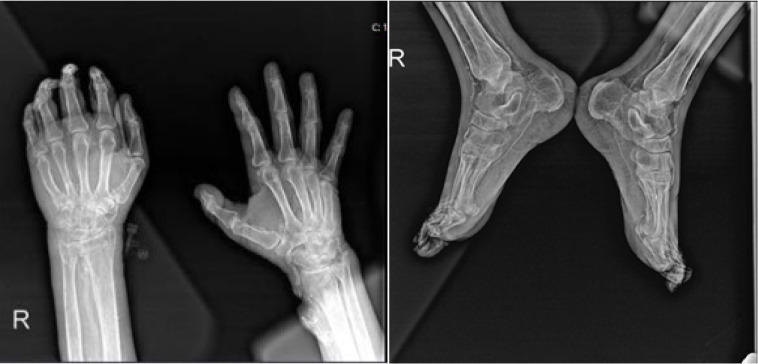

钙化反应,字面意思是“通过钙化来保护”,是一种致命的疾病,其特征是由血管内膜纤维增生、血栓和小动脉钙化引起的皮肤组织缺血性坏死。病理生理学涉及由于血清钙、磷和甲状旁腺激素(PTH)水平异常导致的钙在皮肤、血管间隙和脂肪组织中的积累,特别是在终末期肾病(ESRD)患者中。临床表现通常包括严重的缺血性和神经性疼痛,这些疼痛可能独立于皮肤病变而发生。没有具体的诊断标准或实验室检查;这种疾病主要是根据临床发现来识别的。由于对其机制的了解不完全,没有关于治疗的明确信息;因此,预防钙化反应是至关重要的。在对文献中的病例进行检查后,尽管得到了适当的治疗和护理,但仍观察到34%的死亡率。鉴于其罕见性,钙化反应很容易被忽视。通过对我们风湿病诊所的两例病例的回顾,我们的目的是提高人们对类似血管炎的钙化反应的认识,并促进早期诊断。

Calciphylaxis, which literally means 'protection through calcification', is a fatal disease characterised by ischemic necrosis of cutaneous tissue resulting from vascular intimal fibroplasia, thrombi, and calcifications in the arterioles. The pathophysiology involves the accumulation of calcium in the skin, vascular space, and adipose tissue due to abnormal serum levels of calcium, phosphorus, and parathyroid hormone (PTH), particularly in patients with end-stage renal disease (ESRD). The clinical presentation typically involves severe ischemic and neuropathic pain, which may occur independently of skin lesions. There are no specific diagnostic criteria or laboratory tests; the disease is primarily recognised based on clinical findings. There is no definitive information on treatment due to the incomplete understanding of its mechanism; therefore, the prevention of calciphylaxis is of paramount importance. Upon examination of cases in the literature, a mortality rate of 34% is observed despite appropriate treatment and care. Given its rarity, calciphylaxis is prone to being overlooked. Through this review presenting two cases seen in our rheumatology clinic, our aim is to raise awareness about calciphylaxis which can mimic vasculitis, and promote early diagnosis.